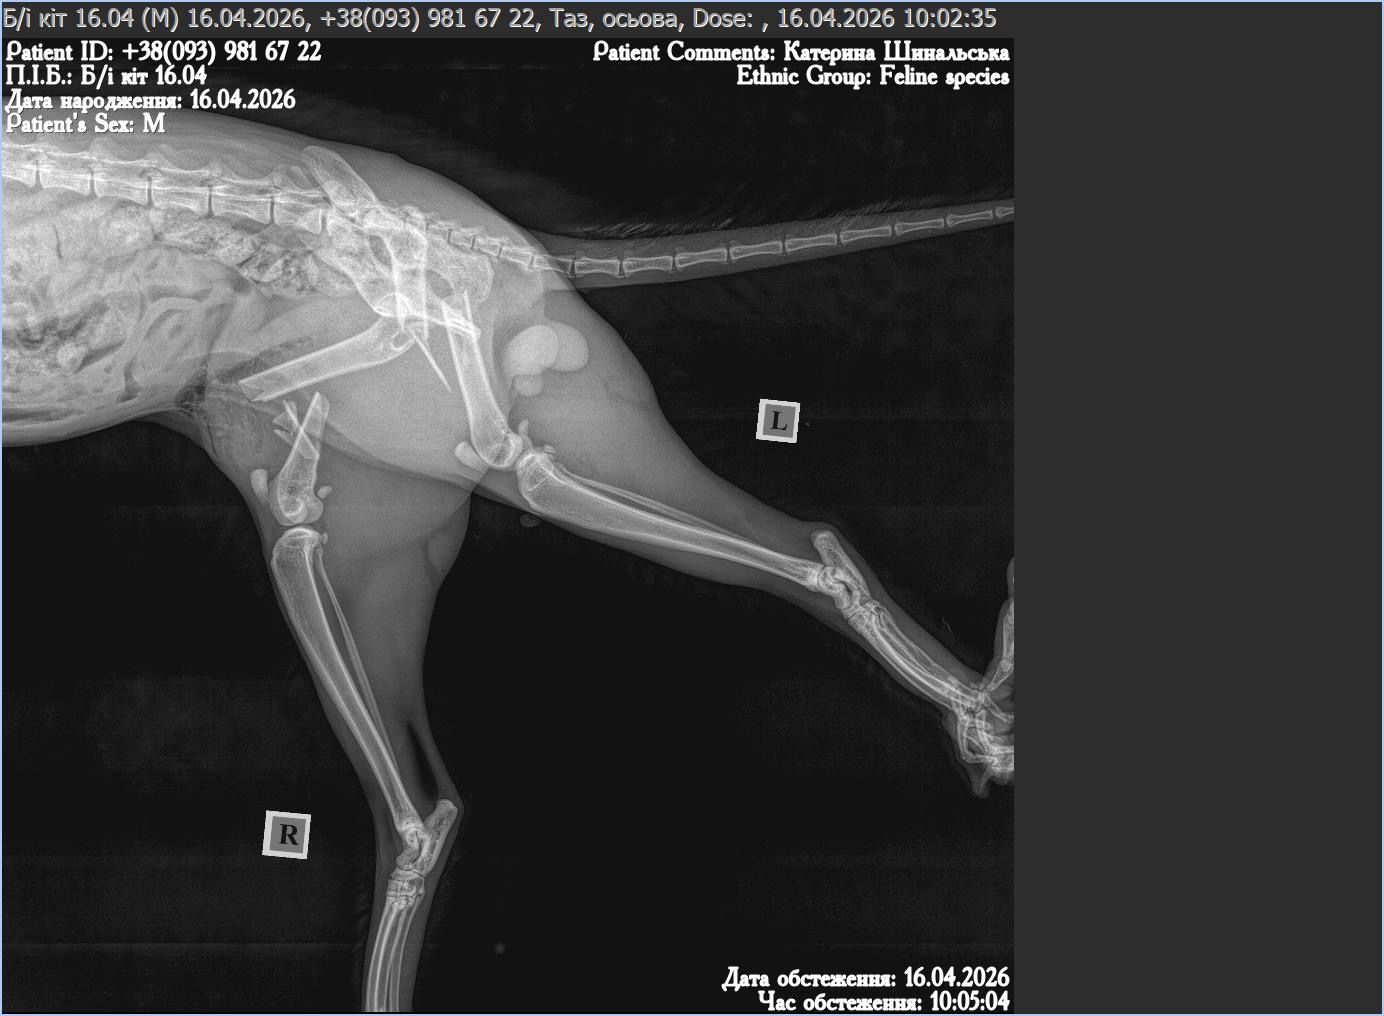

Droga gdzieś w Ukraina i on — małe ciało leżące nieruchomo. Nie ucieka, nie podnosi się, nawet nie próbuje. Obie tylne łapki złamane, biodro przemieszczone. Ciało, które jeszcze chwilę temu było szybkie i żywe, nagle przestaje działać.

Operacja jest długa i skomplikowana. W jego ciele zostaje specjalna konstrukcja, która ma utrzymać kości i dać im szansę się zrosnąć.